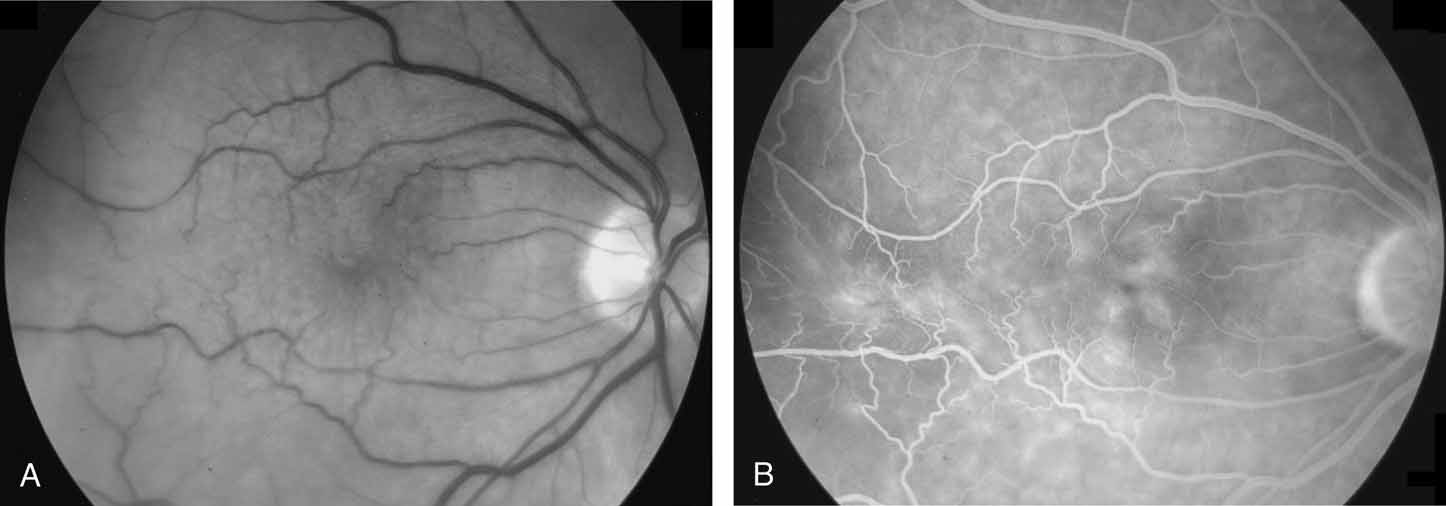

The clinical appearance is variable and may present as only a mild sheen or glint in the macular region that can best be seen with red-free or monochromatic green or blue light (Fig. 5). In more severe cases, there is increased vascular tortuosity and the perimacular vessels are seen to be pulled toward an epicenter, with striae and heterotopia of the macula. The superior and inferior arcuate vessels are also closer together and straighter than in an uninvolved eye. Other findings that may be present include small intraretinal hemorrhages, cystic changes in the macula, macular edema, and cotton-wool spots.110 Pseudoholes or macular cysts have been noted in up to 8% of idiopathic cases (Fig. 6).25,88 Thin membranes may be completely translucent, whereas thicker membranes are frequently opaque or pigmented and generally obscure details of the underlying fundus (Fig. 7).110–112 The thicker and occasionally pigmented membranes are often seen after retinal detachment surgery, severe inflammatory conditions, and trauma. An apparent posterior vitreous separation has been reported by most authors to exceed 75% in cases of idiopathic epiretinal membranes.84–88,93,104,105,113–117 It is sometimes difficult to accurately determine the vitreoretinal relationships preoperatively.

Fig. 5 A. An idiopathic epiretinal membrane in a 65-year-old man. Visual acuity was 20/25. B. Black-and-white fundus photograph taken with green 540-nm filter. Note increased definition of epiretinal membrane. (Margherio RR: Epiretinal macular membranes. In Albert R, Jakobidc EA, eds. Principles and Practice of Ophthalmology, Vol. 2. Philadelphia: WB Saunders, 1993:919–925)

Clinical testing, in addition to visual acuity, most commonly involves fluorescein angiography and ocular coherence tomography. Fluorescein angiography can show retinal vascular tortuosity, straightening, and leakage, as well as cystoid macular edema (Fig. 8). OCT typically demonstrates retinal folding, increased macular thickness, cystoid macular edema, traction macular retinal detachment, and both lamellar or macular hole formation (Figs. 9, 10, and 11). Sine Amsler chart testing may help quantify metamorphopsia in eyes with macular distortion.118 Abnormal macular function has been shown using both focal and multifocal electroretinography.119,120

Fig. 8 A. Black and white photograph taken with a green 540-nm filter, showing dragging and distortion of the macular vessels. B. Fluorescein angiogram. Note distortion of macula and vessels, with associated vascular leakage and cystoid macular edema.